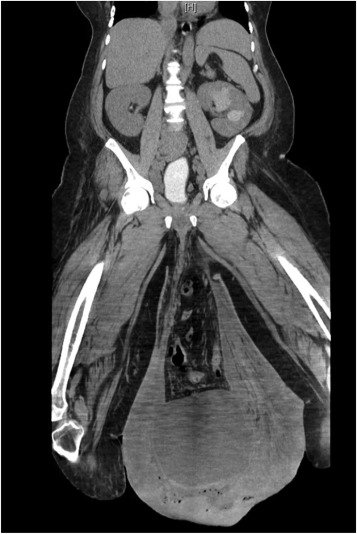

Conséquence, la maladie s’aggravait de plus en plus, qu’il ne pouvait même plus se déplacer à cause de son pénis qui pesait trop lourd et qui touchait presque le sol. Son scrotum mesurait en fait 30,2 cm x 24,4 cm x 13,1 cm.

Après consultation, les médecins ont diagnostiqué chez ce patient la gangrène de Fournier, une maladie rare mais mortelle, car elle tue rapidement les tissus. Mais son état est encore aggravé par le lymphoedème massif qui se manifeste par le gonflement du scrotum et de sa jambe droite.

Après avoir fait passer une tomodensitométrie de l’abdomen, les médecins ont également découvert une hernie massive, ainsi qu’un gros abcès sous la peau, ce qui a aggravé encore plus sa situation. À cause de l’accumulation de l’urine, son rein s’est aussi enflé et sa peau était en train de pourrir.